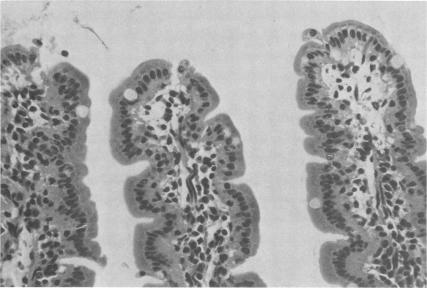

Botulinum C2 toxin has histopathological activity in the mouse intestine and induces fluid accumulation in intestinal loops. The toxin caused degenerative and necrotic changes in the intestinal mucosa: intracellular vacuolization of epithelial cells, desquamation and necrosis of the villous epithelium, intercellular edema, and infiltration of lymphocytes and histiocytes. The detectable changes in the morphology of the intestinal mucosa preceded the increase in fluid accumulation in intestinal loops. Intraluminal injection of botulinum C2 toxin also induced the leakage of plasma protein into the intestinal lumen as determined by the extravasation of Evans blue. In contrast to botulinum C2 toxin, cholera and Clostridium perfringens enterotoxin controls caused a very slight protein leakage, although these toxins induced marked fluid accumulation in intestinal loops. The results indicate that the mode of action of botulinum C2 toxin in eliciting the secretory response is distinguishable from those of cholera and C. perfringens enterotoxins and suggest that botulinum C2 toxin induces the secretory response by cytopathic effect(s) on the epithelial cells of the intestine.

肉毒杆菌C2毒素在小鼠肠道具有组织病理学活性,并可诱导肠袢积液。该毒素导致肠黏膜发生退行性和坏死性改变:上皮细胞内出现空泡化、绒毛上皮脱落和坏死、细胞间水肿以及淋巴细胞和组织细胞浸润。肠黏膜形态学上可检测到的变化先于肠袢积液增加。通过伊文思蓝外渗测定,肠腔内注射肉毒杆菌C2毒素还可诱导血浆蛋白渗漏至肠腔内。与肉毒杆菌C2毒素相反,霍乱毒素和产气荚膜梭菌肠毒素对照引起的蛋白渗漏非常轻微,尽管这些毒素可诱导肠袢显著积液。结果表明,肉毒杆菌C2毒素引发分泌反应的作用方式与霍乱毒素和产气荚膜梭菌肠毒素不同,提示肉毒杆菌C2毒素通过对肠道上皮细胞的细胞病变效应诱导分泌反应。